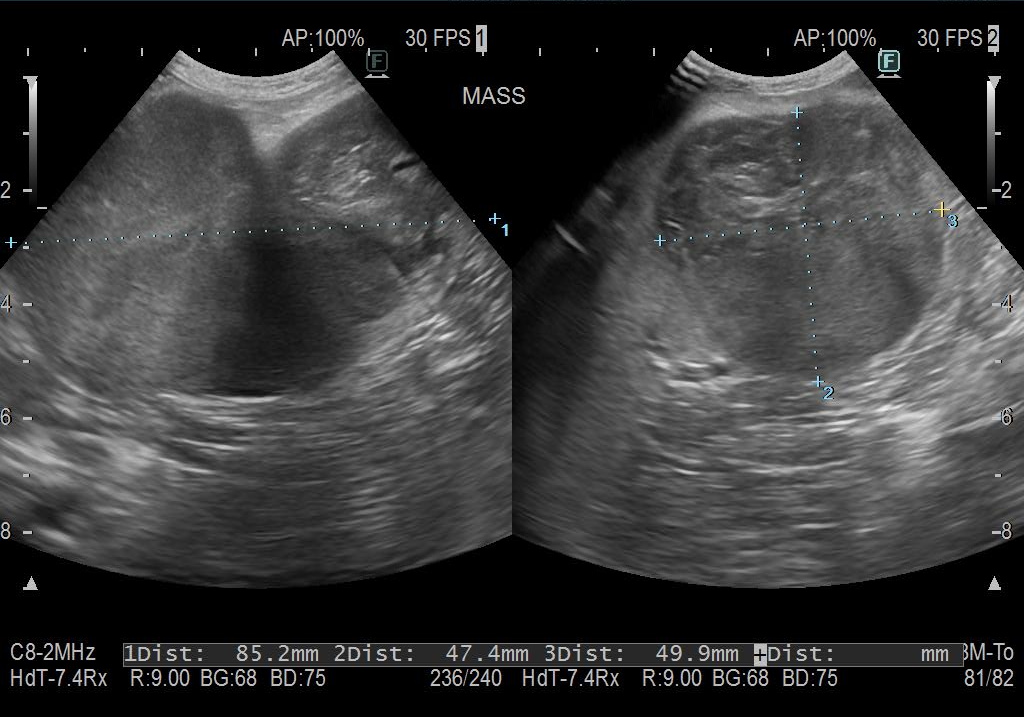

レントゲン検査、超音波検査にて脾臓に大きなしこりが見つかりました。

(今回の胃腸障害・発熱は、脾臓のしこりが小破裂をしたところにお腹の中の脂肪が癒着したため炎症が起きて腹膜炎に繋がったためと推測されました)